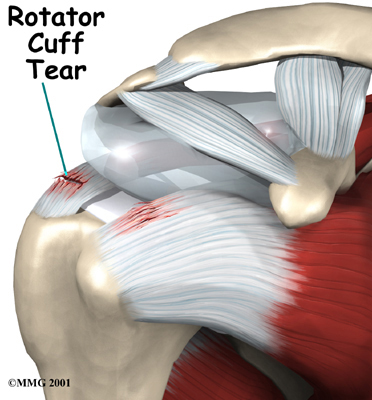

Rotator Cuff Tendonitis

Rotator cuff tendonitis refers to inflammation of the rotator cuff due to repeated stress (e.g., throwing, overhead lifting). This injury is also described as shoulder impingement, biceps tendonitis, or shoulder bursitis. Rotator cuff tendonitis often leads to chronic pain, even while at rest.

The upper portion of the arm bone, called the humerus, is connected to the shoulder by tendons and muscles. Four of these tendon-muscle groups form what is known as the rotator cuff—the structure that stabilizes the shoulder and controls the lifting of the arm.

Rotator cuff problems can range from mild damage to partial or complete tears. If left untreated, a severely torn rotator cuff may require surgical treatment.